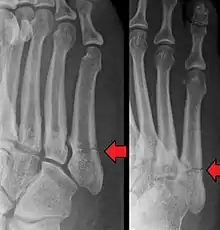

Jones fracture as seen on Xray

A Jones fracture is a broken bone in a specific part of the fifth metatarsal of the foot between the base and middle part[8] that is known for its high rate of delayed healing or nonunion.[4] It results in pain near the midportion of the foot on the outside.[2] There may also be bruising and difficulty walking.[3] Onset is generally sudden.[4]

Diagnosis

A person with a Jones fracture may not realize that a fracture has occurred. Diagnosis includes the palpation of an intact fibularis brevis tendon, and demonstration of local tenderness distal to the tuberosity of the fifth metatarsal, and localized over the shaft of the proximal metatarsal.

Diagnostic X-rays include anteroposterior, oblique, and lateral views and should be made with the foot in full flexion.